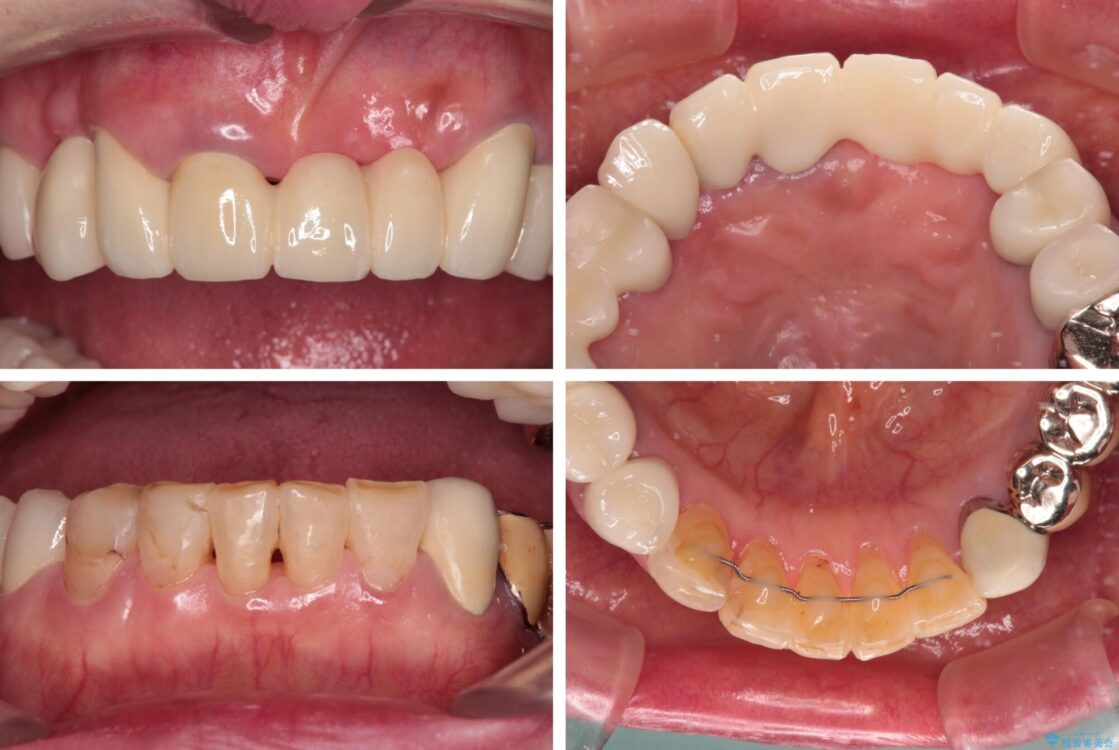

治療途中

• 前歯をきれいにしたい インプラントや部分矯正を用いた総合歯科治療 治療途中画像